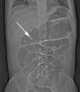

Neonatal adynamic ileus

Acute nonobstructive small bowel distention

Intestinal pseudo-obstruction